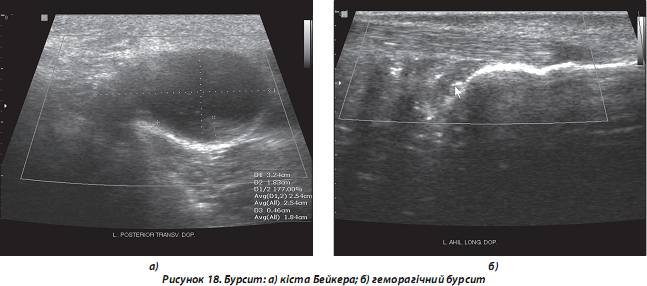

3. Патологія суглобових сумок (бурсити):

а) гострий та хронічний бурсит: частіше спостерігаються у верхньому та задньому заворотах колінного суглоба, міжфасціальних просторах гомілки (особливо при розриві кісти Бейкера) (рис. 18а), субакроміально-субдельтоподібній, ліктьовій, позап’ятковій сумках; рідше спостерігаються інші локалізації бурситів. УЗ-ознаки — збільшення розмірів сумки, анехогенна зона в проекції ураженої сумки (наявність вільної рідини), обмежена гіперехогенною оболонкою (стінка сумки);

б) геморагічний бурсит: виникає внаслідок прямої/непрямої травми даної ділянки, розриву прилеглого сухожилля/сухожиль, перелому кісток, патології згортання крові тощо. УЗ-ознаки: розміри суглобової сумки більші, ніж при звичайному гострому бурситі, стадійність змін ехоструктури вільної рідини в порожнині сумки швидка (див. нижче диференційні ознаки гострого та хронічного бурситу) (рис. 18б).

Диференційними УЗ-ознаками гострого та хронічного бурситу є:

1. Товщина стінки сумки (при гострому бурситі стінки тонкі, при хронічному — товсті, досить часто з нерівними контурами).

2. Особливості ехоструктури рідини в порожнині сумки (при гострому бурситі — гомогенна анехогенна, при хронічному часто негомогенна, з наявністю ехопозитивних включень різного розміру та ехощільності), рухомих при проведенні функціональних проб.

3. Наявність васкуляризації при допплерівському дослідженні (при гострому бурситі найчастіше кровотік у стінці сумки відсутній, при хронічному спостерігається часто).